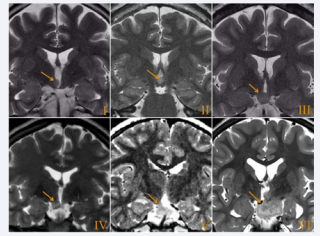

There have been used several HH classifications based on anatomical features seen on neuroimaging [53]. HH can be pedunculated or sessile. The former ones are attached to the tuber cinereum and project into the suprasellar cistern. Sessile HH are attached to the floor of the 3rd ventricle and often incorporate the mammillary bodies. Projection into the suprasellar cistern is variable. We use the classification described by Regis et al., which correlates their topology with clinical semiology and its severity, and is especially critical for the selection of treatment [54,55] (Figure 3).

Topological classification of HH [55]. (Type I) - Small HH located  inside the hypothalamus extending more or less in the 3rd ventricle. (Type  II) - Small lesion and located primarily in the 3rd ventricle. (Type III) - Lesion  essentially located on the floor of the 3rd ventricle. (Type IV) - Sessile lesion in  the cistern. (Type V) - Pedunculate. (Type VI) - Giants.

Figure 3: Topological classification of HH [55]. (Type I) - Small HH located inside the hypothalamus extending more or less in the 3rd ventricle. (Type II) - Small lesion and located primarily in the 3rd ventricle. (Type III) - Lesion essentially located on the floor of the 3rd ventricle. (Type IV) - Sessile lesion in the cistern. (Type V) - Pedunculate. (Type VI) - Giants.